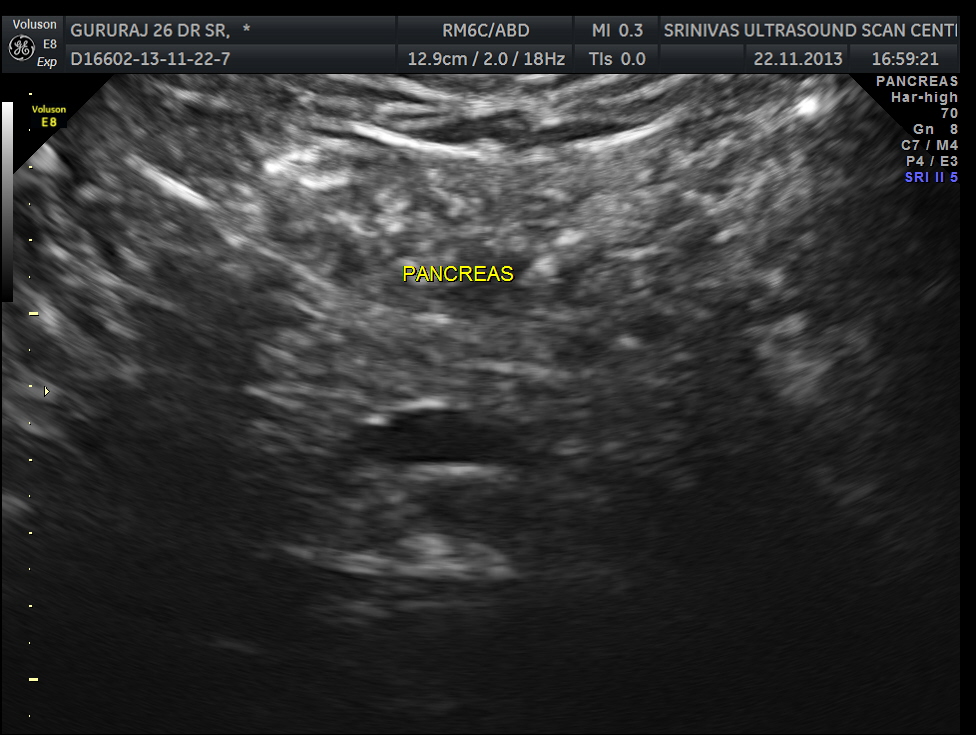

An ultrasound abdomen was done as part of evaluation of anemia.